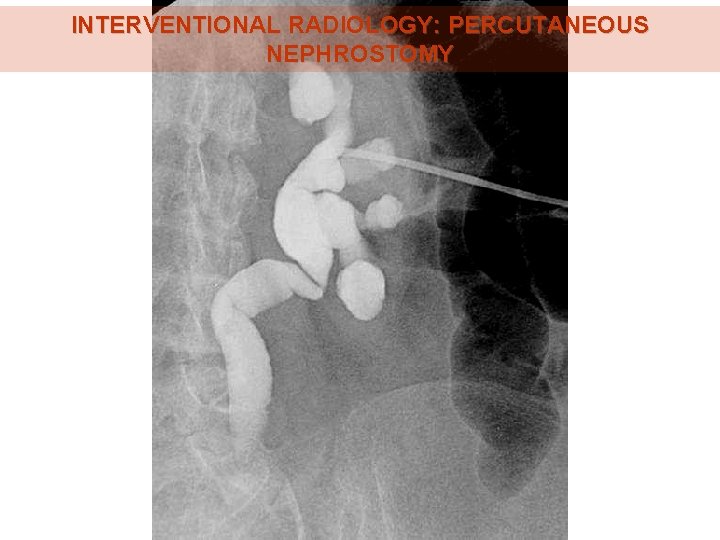

INTERVENTIONAL RADIOLOGY: PERCUTANEOUS NEPHROSTOMY